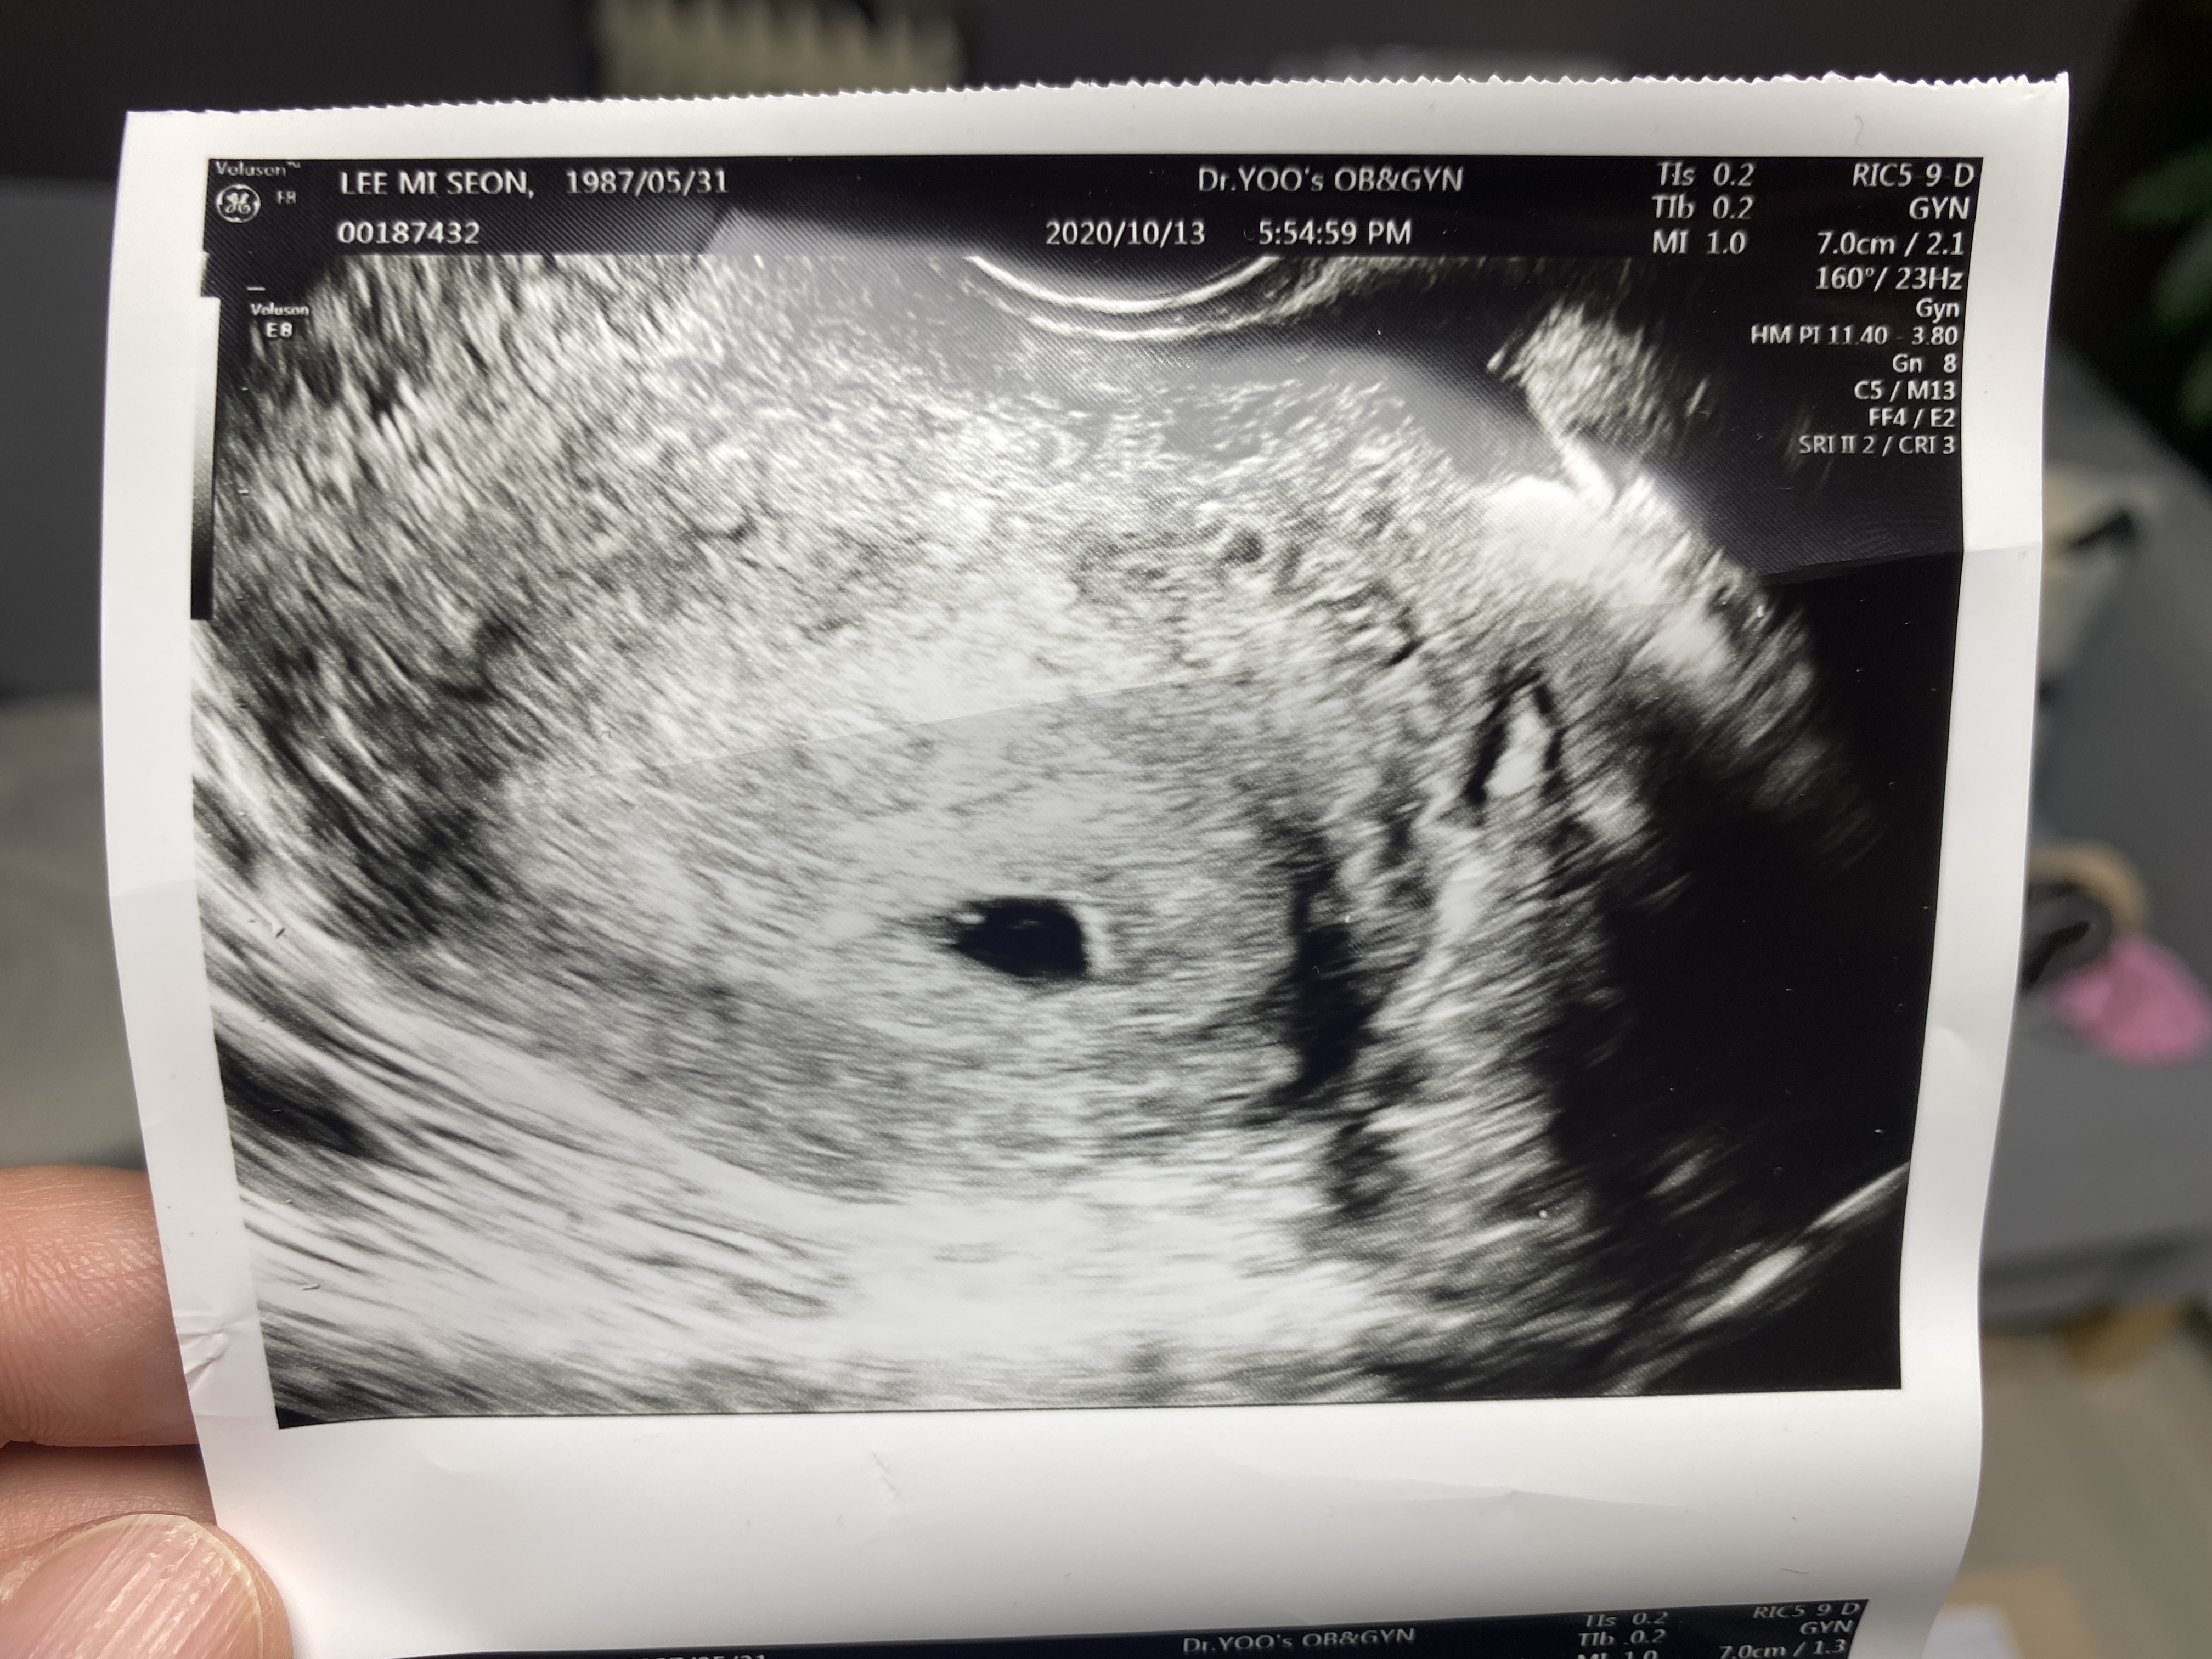

오늘은 5주2일째, 아기집을 볼 수 있는 날이라 오후 반차를 내고 와이프와 병원에 다녀왔다

그리고 오늘 초음파로 와이프 뱃속에 떡! 하니 만들어 놓은 아기집을 확인하고는

와이프와 나는 어떻게 말도 못 할 안도의 한숨을 내쉰 듯하다

아기집 크기는 0.9mm 크기로 주수에 비해서 0.3mm는 더 크다고 하시는데